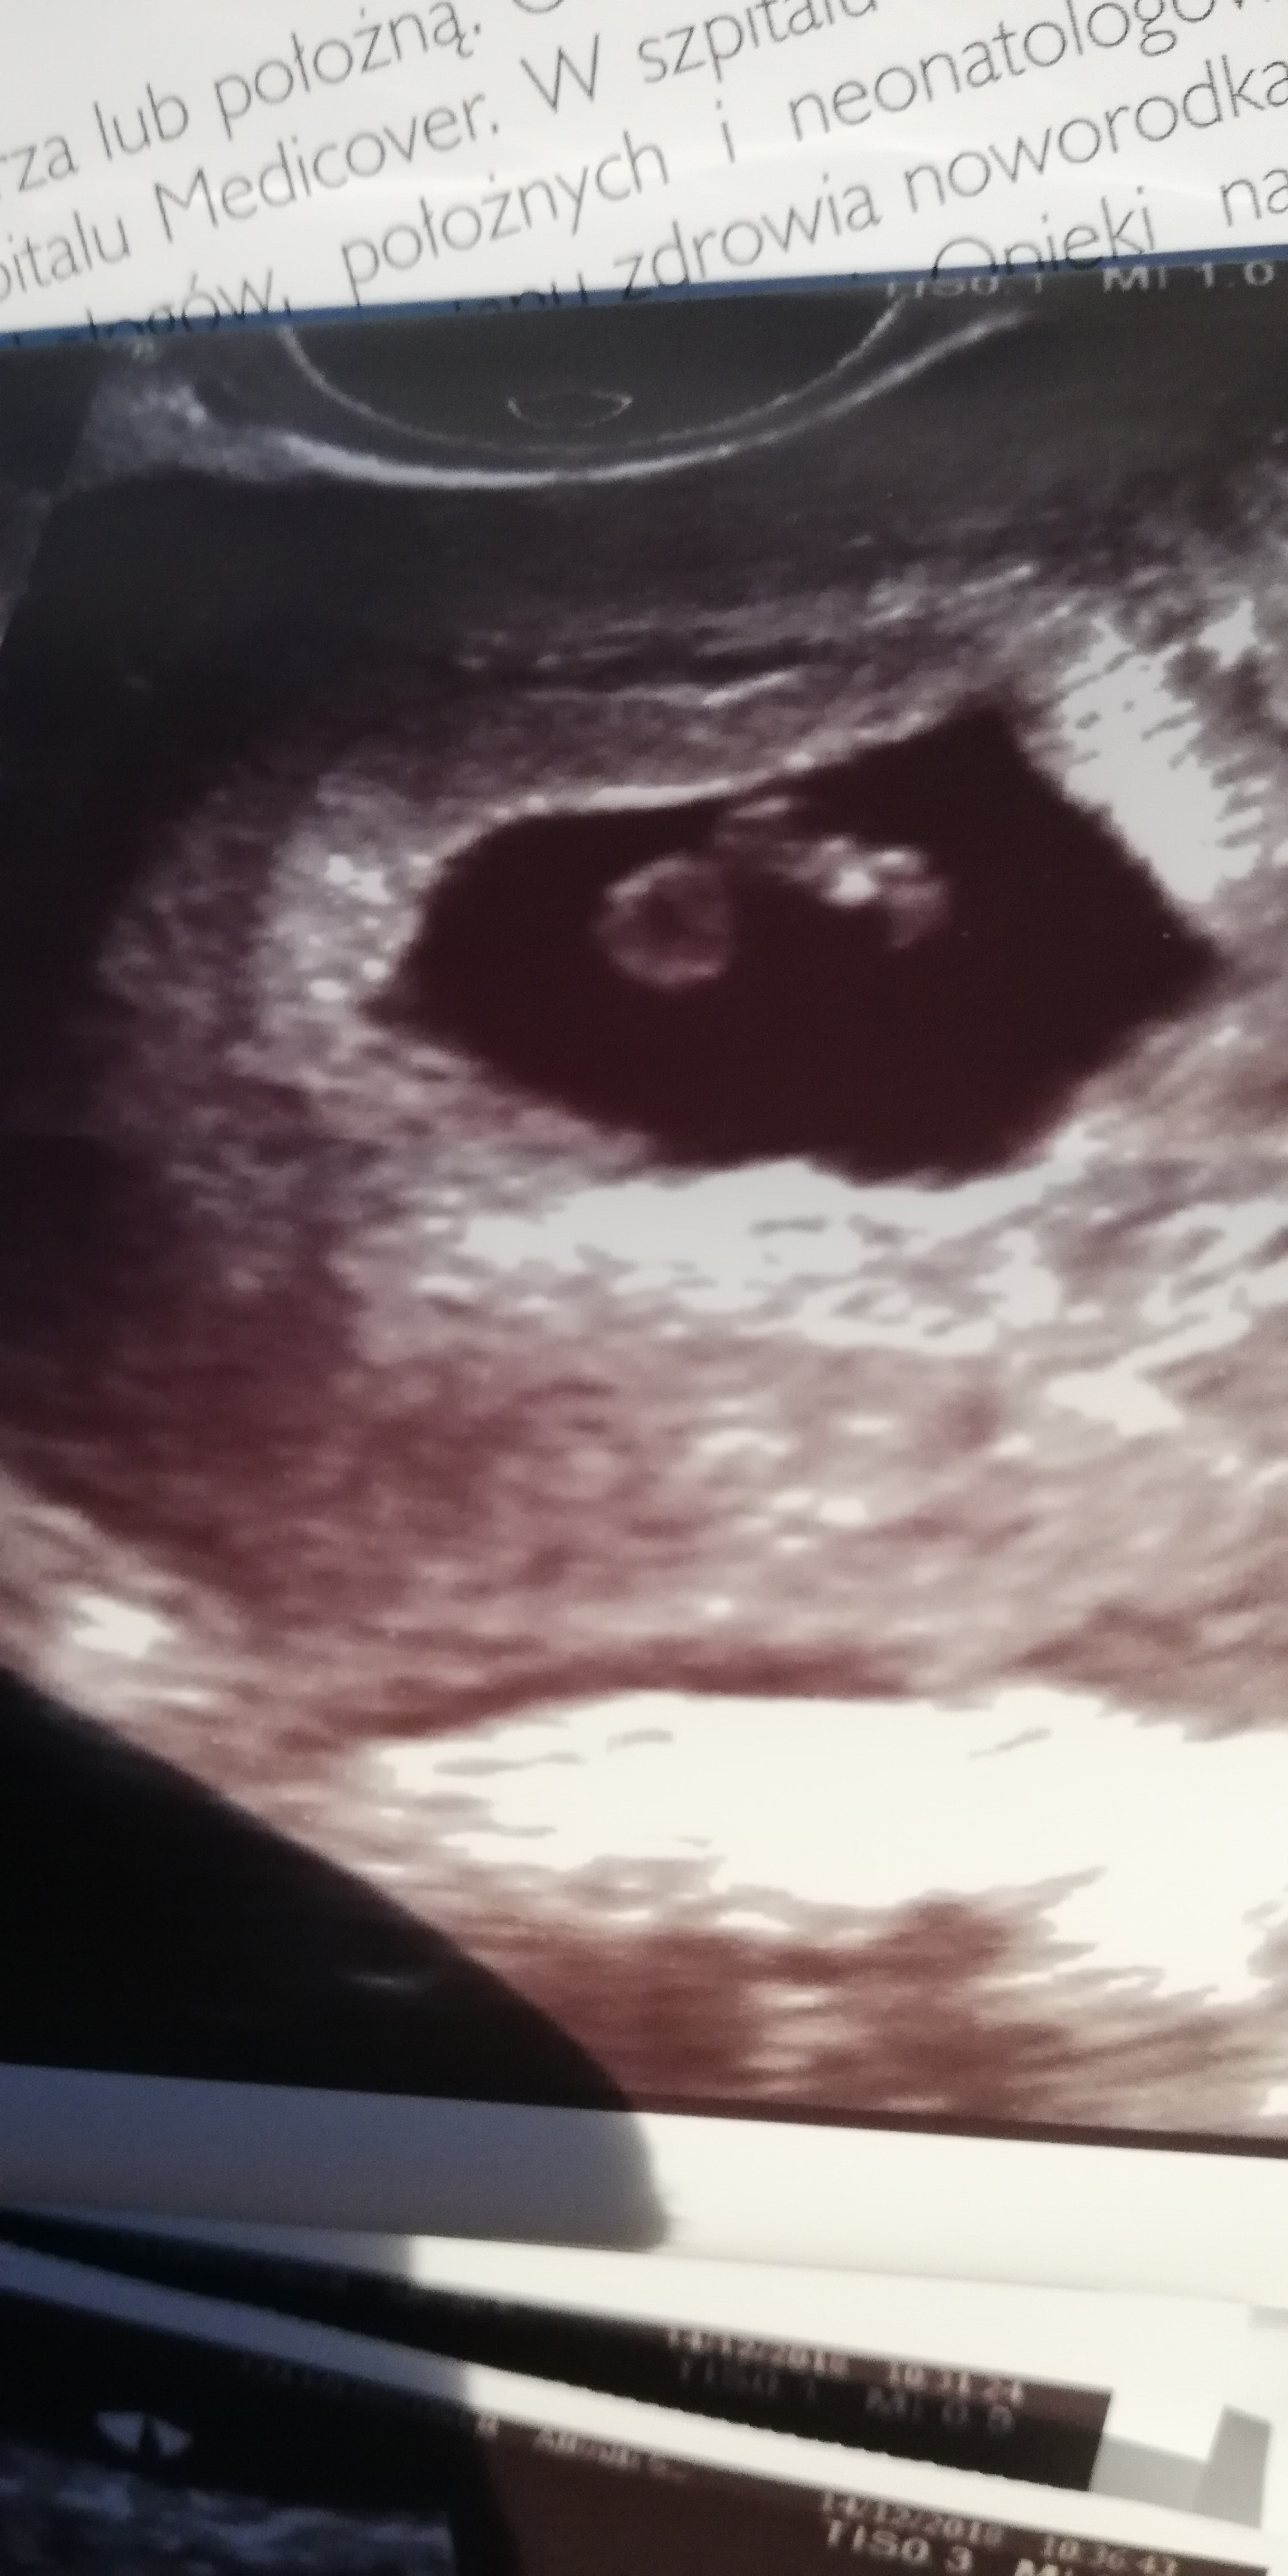

u mnie też fajnie było widać na pierwszym zdjęciu :) pęcherzyk, w środku ciałko żółte i zarodek z serduszkiem.

ogólnie na usg ciąży raczej zawsze jest data ostatniej @ (LMP albo OM), termin przewidywanej daty porodu (EDD) i wiek ciąży (GA).

no i inne typu wielkość pęcherzyka (GS), zarodka jeśli jest (CRL), bicie serduszka (FHR)